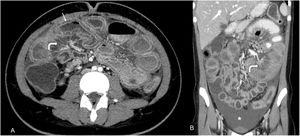

Abdominal CT scan – dilatation of intestinal segments, with circumferential, multisegmented mural thickening of over 3mm, affecting mainly the jejunum and descending colon, with associated submucosal oedema (“target sign” – arrow) and ascites (*). There is engorgement of mesenteric vessels and mesenteric fat stranding (curved arrows), suggesting vasculitis.

A previously healthy 19-year-old Caucasian female presented with severe abdominal pain, fever, vomiting, and watery diarrhoea for two weeks despite supportive care. Physical examination revealed fever, hypotension, and a tender abdomen. Laboratory tests showed mild leucocytosis, thrombocytopenia (73,000/μL), increased C-reactive protein and lactate dehydrogenase. Cultures and serologies ruled out an infection, while elevated faecal calprotectin levels were noted (783mg/kg). Contrast-enhanced computed tomography (CT) displayed mural thickening of the jejunum and descending colon with submucosal oedema (“target sign”) and ascites (Fig. 1). Upper endoscopy was unremarkable, while colonoscopy revealed diffuse nonspecific oedema and erythema of the descending colon, without any erosions, active bleeding or ulceration. The patient was hospitalised. Histopathology of the colon samples revealed nonspecific inflammation with focally increased intraepithelial lymphocytes. Further study revealed positive anti-nuclear (1/1280 titer, nuclear homogeneous pattern), and anti-double-stranded DNA antibodies (449IU/mL), and hypocomplementemia. Systemic lupus erythematosus (SLE) with lupus enteritis was diagnosed in accordance with the ACR/EULAR classification scoring 16 points. Treatment with intravenous methylprednisolone pulses followed by cyclophosphamide led to clinical recovery.

Lupus enteritis is an uncommon and severe manifestation of systemic lupus erythematosus involving mesenteric vasculitis and inflammatory changes within the intestinal wall. The submucosal oedema is responsible for the “target sign” appearance on CT, demonstrating attenuation of the submucosa enclosed by inner and outer circumferential enhancement of the thickened intestinal wall. The engorgement of mesenteric vessels, increased attenuation of mesenteric fat may be present, indicating underlying vascular inflammation.1 Since lupus enteritis may be the presenting feature of SLE, its recognition in the appropriate context should prompt ANA screening and treatment initiation to prevent bowel ischemia and perforation.1,2